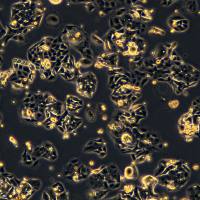

细胞名称:3dGRO® Pancreatic Organoids (OCIP.335)

特点和优势:Cryopreserved patient derived pancreatic cancer organoids (PDOs)

储存及稳定性:Store in liquid nitrogen. The organoids can be cultured for at least 10 passages after initial thawing without significantly affecting the cell marker expression and functionality.

类器官分化流程。人结肠类器官可以通过定形内胚层、后肠内胚层和结肠类器官扩增阶段,使用三步分化方案从人 iPS 细胞生成。 SCM302:定形内胚层诱导培养基,SCM303:后肠诱导培养基,SCM304:3dGRO™ 人结肠类器官扩增培养基 类器官培养方案 步骤1:人 iPS 细胞分化为定形内胚层(第 0-4 天) 注意:起始材料为高品质未分化的人 ES/iPS 细胞(SCC271)(细胞融合度约为 70-80%,且含有 准备单细胞传代培养基。将 ROCK 抑制剂 (ROCKi) Y

在自然界,许多动物拥有着令人惊叹的再生能力,比如「超级选手」海星、蝾螈、斑马鱼(心脏可再生)、扁虫(头部可再生)……科学家们一直希望将这些神奇应用于生命科学,解决器官移植、药物开发等问题。干细胞是组织再生的「源泉」,在此基础之上诞生的「类器官」(organoids)给予了更多的可能。这些在体外培养的微小结构,可以模拟人体器官的复杂结构,还可以重塑体内肿瘤组织的关键特性,有着代替动物试验、实现器官移植的巨大潜力。类器官的获得与治疗潜能01 助力精准医学的「秘密武器」自 2000 年代末,生物